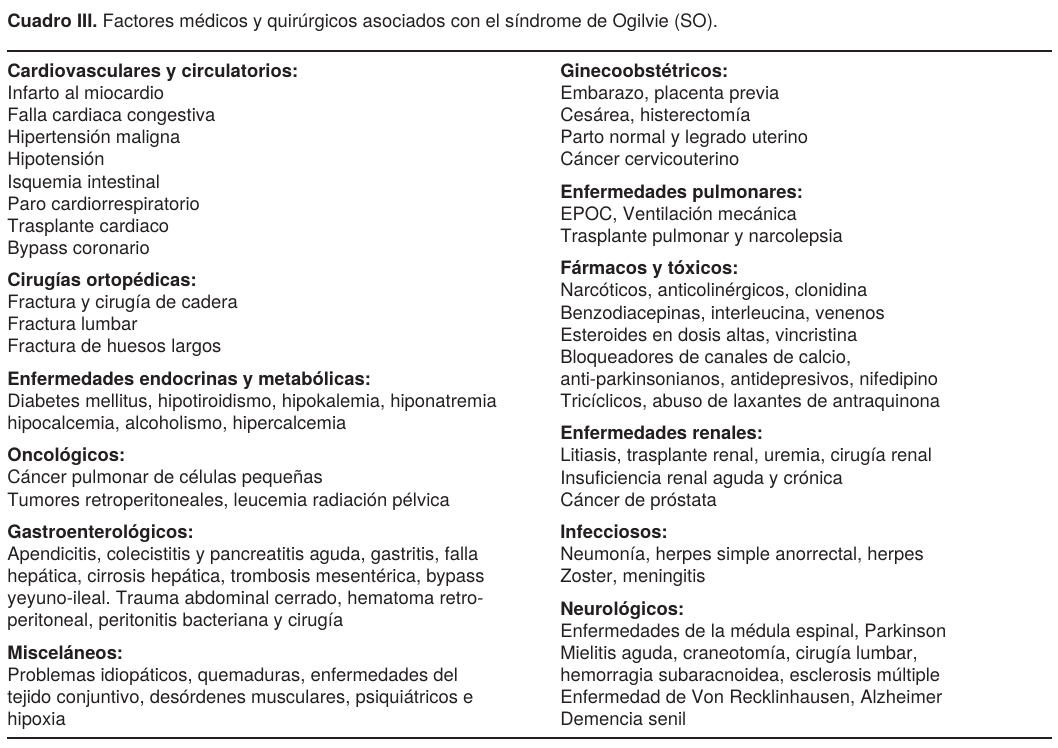

Se caracteriza por una distensión abdominal moderada a severa acompañada de disnea, dolor tipo cólico en hipogástrio, puede cursar con estreñimiento y/o dificultad para canalizar gases y en casos raros puede haber diarrea. En la exploración del abdomen existe timpanismo generalizado, los ruidos peristálticos pueden estar disminuidos o ausentes. Al principio del cuadro clínico no hay signos peritoneales y el recuento de leucocitos es normal, sobre todo en paciente con una evolución progresiva, hospitalaria (3 a 7 días); secundaria a una intervención quirúrgica o tratamiento médico. También hay una forma de presentación súbita (24 a 48 h); el desequilibrio electrolítico se acompaña en esta fase con náusea y vómito, además existen signos de irritación peritoneal por perforación, posibilidad de neumoperitoneo y peritonitis. Es importante tener los antecedentes personales patológicos del paciente y causas que con mayor frecuencia se asocian a este síndrome, para tratar de evitar una confusión diagnóstica y provocar una iatrogenia (Cuadro III).